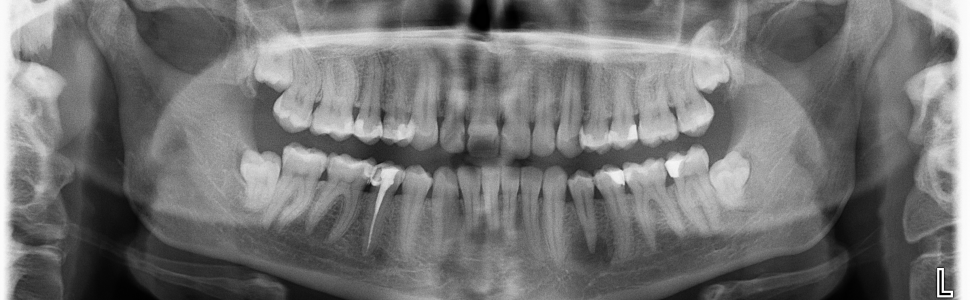

Dysplazja kostniwno-kostna okołowierzchołkowa to najczęstsza łagodna zmiana włóknisto-kostna kości żuchwy. W niniejszej pracy przedstawiono proces diagnostyczny oraz opis leczenia endodontycznego zęba 34 przed planowanym leczeniem chirurgicznym pacjentki.